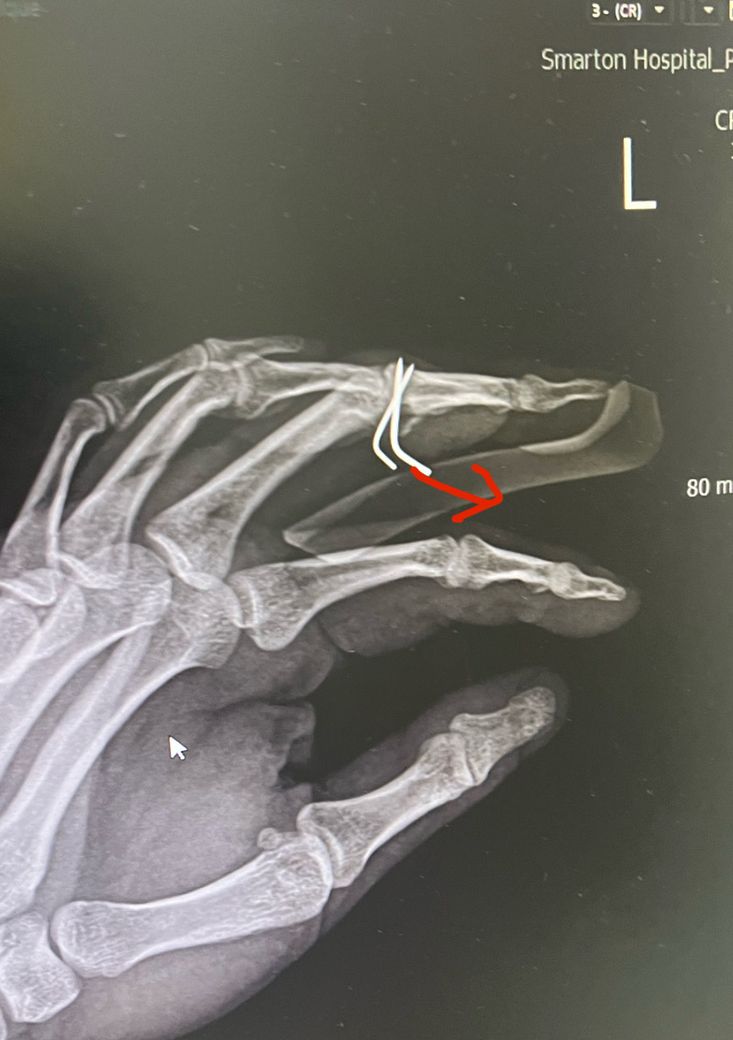

손가락 골절 수술 후 핀제거 했습니다.

1. 핀 제거를 하는데 원래 이렇게 아프게 뽑나요? 집도하신 원장님이 엑스레이 사진 빨간방향으로 잡아 땡기시더라구요.

그래서 제가 “그쪽방향이 아니다” 하니까 반대방향으로 빼던데 이사람이 집도한거 맞나요? 엑스레이도 봣으면서 왜 저 빨간방향으로 땡기는지.. 엄청아팟고 상처가 커졌습니다.

• 2번 째 사진

보통 핀을 뽑을 땐 약간의 통증이 동반되는것은 맞지만 핀을 박았을 때의 각도와 핀이 박힌 방향 그대로 빼는것이 맞지만 "ㄴ" 모양으로 되어있기에 다소 뽑을 때 통증이 동반됐을 가능성이 높습니다.